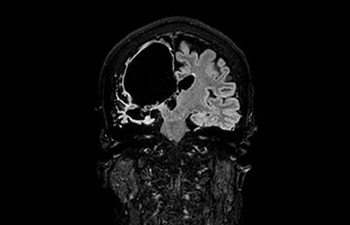

com Compressed SENSE

A equipe de IRM do Hospital Central Kurashiki incorporou o Compressed SENSE à maioria dos protocolos de exames do cérebro, coluna, abdômen e coração do seu Ingenia 1.5T, o que resultou em varreduras de IRM mais rápidas e de alta qualidade, um resultado apreciado por pacientes e pela equipe.